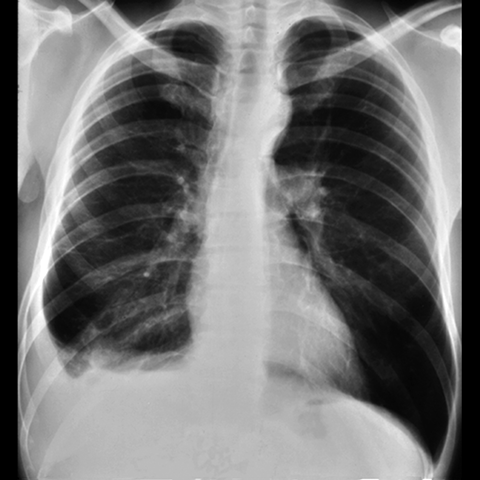

Pleural Effusion, Small to Moderate [2 of 5]